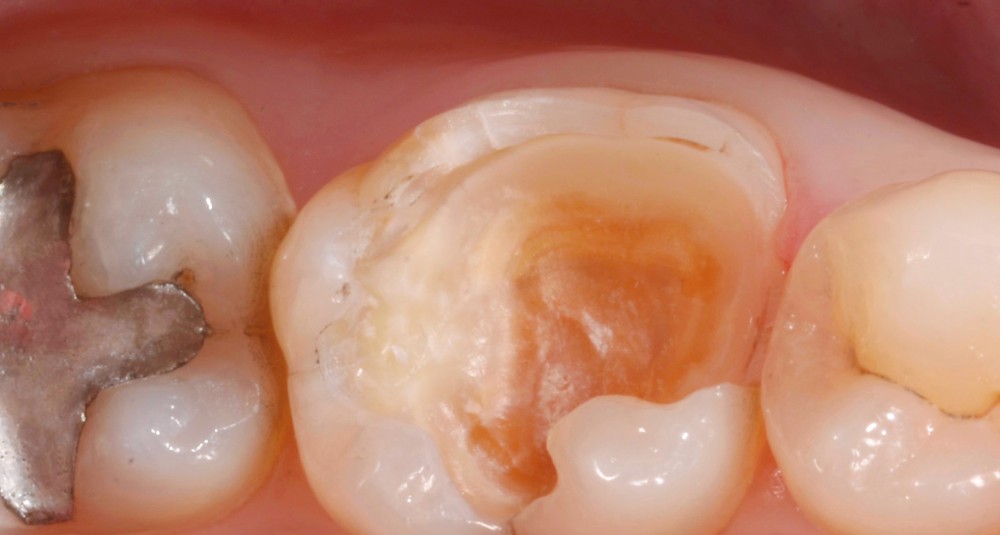

Lors de la préparation d’une cavité pour inlay/onlay, il est fréquent d’être confronté, en fin de nettoyage, à la présence d’une ou plusieurs parois résiduelles dont la résistance mécanique paraît douteuse du fait de leur localisation ou de leur épaisseur. Les parois épaisses (+ de 2 mm) peuvent généralement être conservées (cas clinique 1) et les parois fines (- de 1 mm) doivent généralement être recouvertes. Un inlay (en composite ou en céramique) est alors réalisé. Il doit avoir lui même, au final, une épaisseur globale minimale de 2 mm pour assurer sa résistance mécanique intrinsèque à la mastication. Si un recouvrement cuspidien est indiqué, la réduction occlusale doit donc se faire sur 2 mm de hauteur au minimum [1, 2].

Mais qu’en est-il des parois résiduelles d’épaisseur intermédiaire (entre 1 et 2 mm) (cas clinique 2) ?